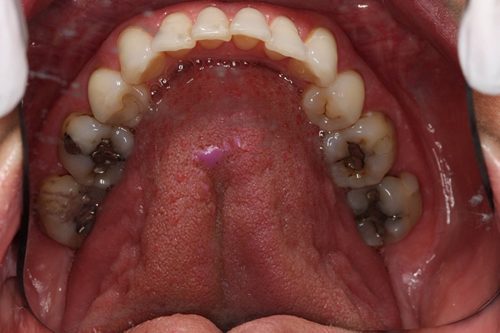

Before